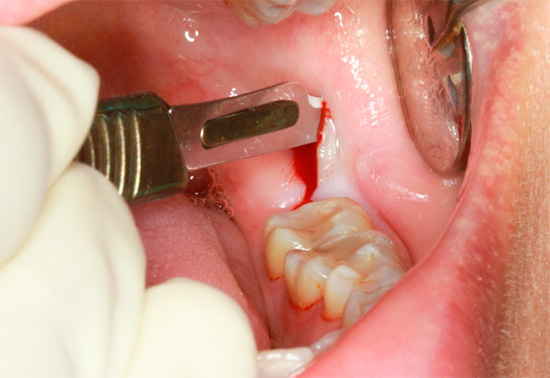

- Remoção complexa. Muitas vezes, durante a remoção complexa devido à falha do médico, há um trauma significativo nos tecidos ao redor do dente que está sendo removido, às vezes a técnica de trabalhar com as ferramentas é interrompida, força e pressão excessivas são aplicadas. No entanto, mesmo com separação complexa (serragem) e remoção das raízes, mesmo das mais imprevisíveis em estrutura e localização na mandíbula da operação do dente do siso, pode ser realizada com tanta precisão (com trauma mínimo) que o inchaço da gengiva e da bochecha quase não ocorre após a remoção.

- Remoção do dente do siso retardado inferior (isto é, que não pode cortar adequadamente). Como regra, a operação para removê-lo é bastante traumática, durante a qual o médico disseca a gengiva e, às vezes, para um melhor acesso, expande bastante a ferida.Devido ao grande número de tecidos bem supridos de sangue, removendo o dente do siso inferior freqüentemente ocorre sangramento abundante e, com lesões significativas nos ossos e na gengiva, um inchaço na bochecha ocorre no primeiro dia após a remoção do dente "sábio".